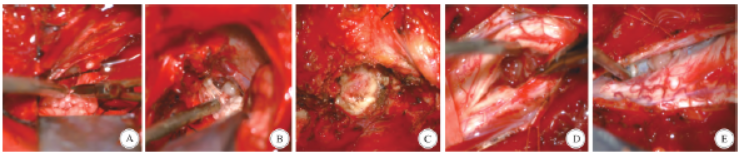

影像学检查提示患者颅内、翼腭窝、头皮下、颈、胸、腰及骶尾部散在占位(图1)。患者行3 次手术依次切除了左侧听神经瘤、左侧颞窝脑膜瘤、左侧翼腭窝区神经鞘瘤、C2 - 7髓内室管膜瘤、颈椎椎管内髓外神经鞘瘤及右侧颞顶枕部皮下神经鞘瘤(图2、图3)。术后病理结果显示左侧桥小脑角区、左侧翼腭窝、右侧颞顶枕部头皮下及颈椎管内髓外的肿瘤为神经鞘瘤,左侧颞窝肿瘤为脑膜瘤,颈椎管内髓内肿瘤为室管膜瘤。

图2 患者术中镜下展示。A、B:第一次手术(切除左侧听神经瘤)在分块切除左侧听神经瘤后,发现在面、三叉及后组颅神经上存在多个类似“葡萄串”一样的肿瘤包裹在神经上;C:第二次手术切除翼腭窝区神经鞘瘤; D、E:第三次手术切除颈椎椎管内髓内、外肿瘤